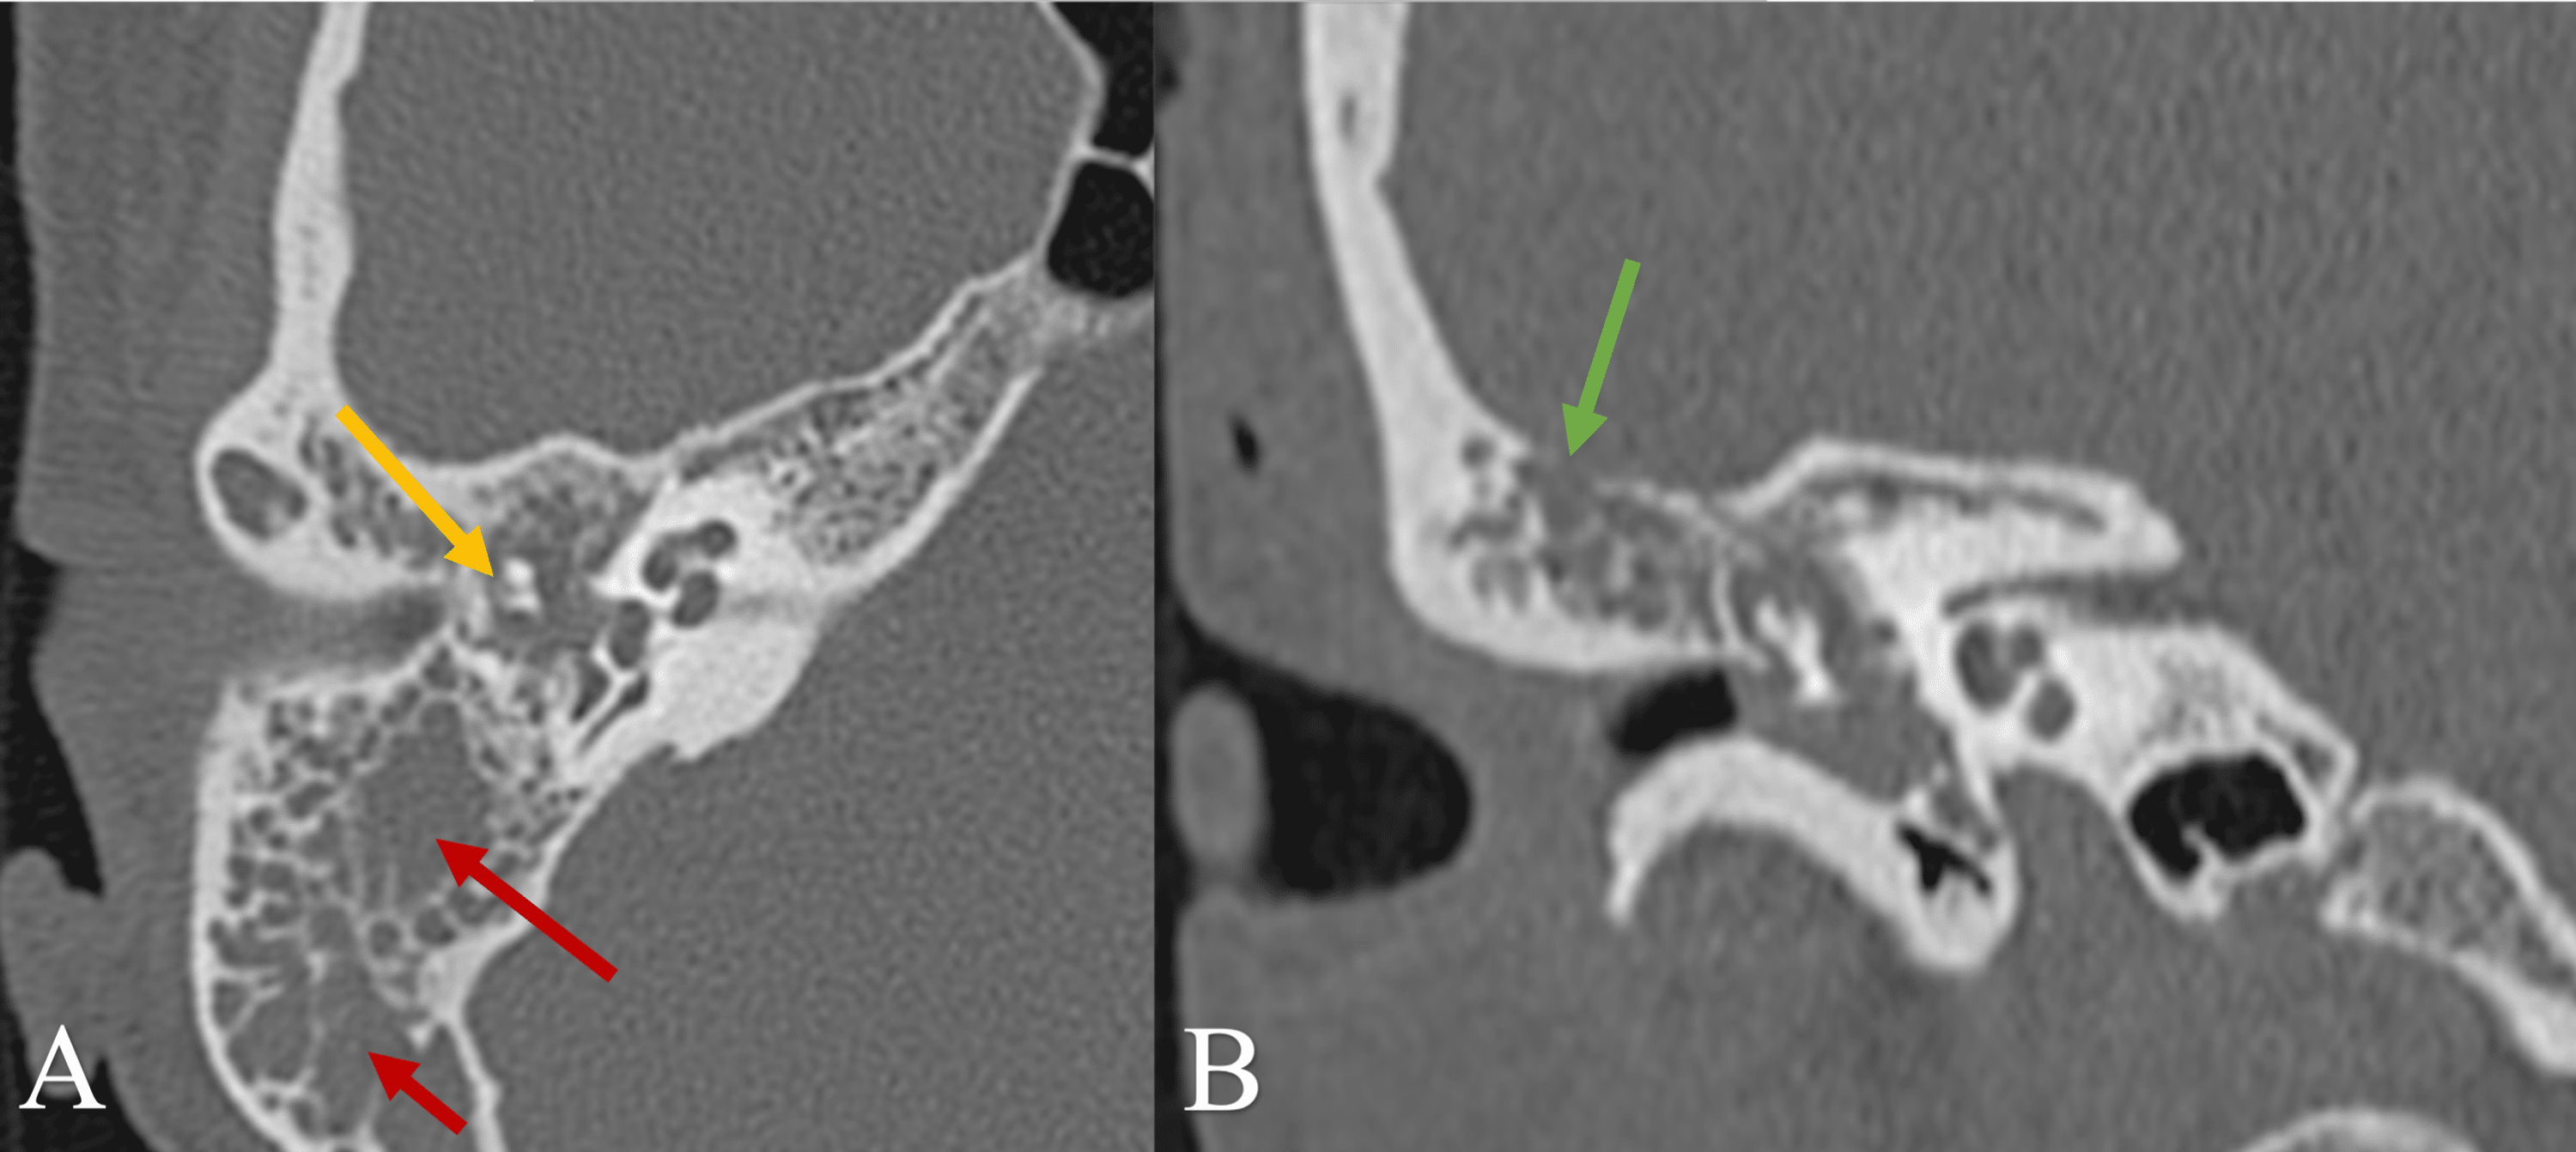

An Unusual Presentation and Diagnosis of a Type 4 Middle Ear Box Middle Ear The middle ear or middle ear cavity, also known as tympanic cavity or tympanum (plural: Coronal section]the middle ear consists of the tympanic cavity, a narrow space located in the petrous part of the temporal bone. The middle ear or middle ear cavity, also known as tympanic cavity or tympanum (plural: Middle ear acts as an amplifying and conducting agent.. Box Middle Ear.